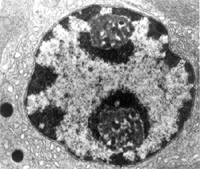

蛋白質促進鈣磷在骨組織中沉積,促進骨細胞間質形成,加速骨鈣化和骨生長。促進組織新生和肉芽形成,加速創傷和潰瘍的修復。降低血膽固醇,改善脂質代謝。為甲睪酮的去氫衍生物,但雄激素作用較小,蛋白同化作用較強。其蛋白同化作用與丙酸睪酮相同,雄激素活性約為後者的1/100,分化指數為3。①能促進蛋白質合成,抑制蛋白質異生,維持正氮平衡,使食慾增進、肌肉增長、體重增加。②促進鈣磷在骨組織中沉積,促進骨細胞間質形成,加速骨鈣化和骨生長。③促進組織新生和肉芽形成,加速創傷和潰瘍的修復。④降低血膽固醇,改善脂質代謝。 臨床用於慢性消耗性疾病、骨質疏鬆症、嚴重感染和創傷燒傷等引起的負氮平衡。